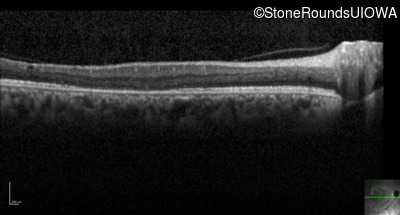

Infrared Fundus Photograph - Left - 20/20 -3

Exemplar